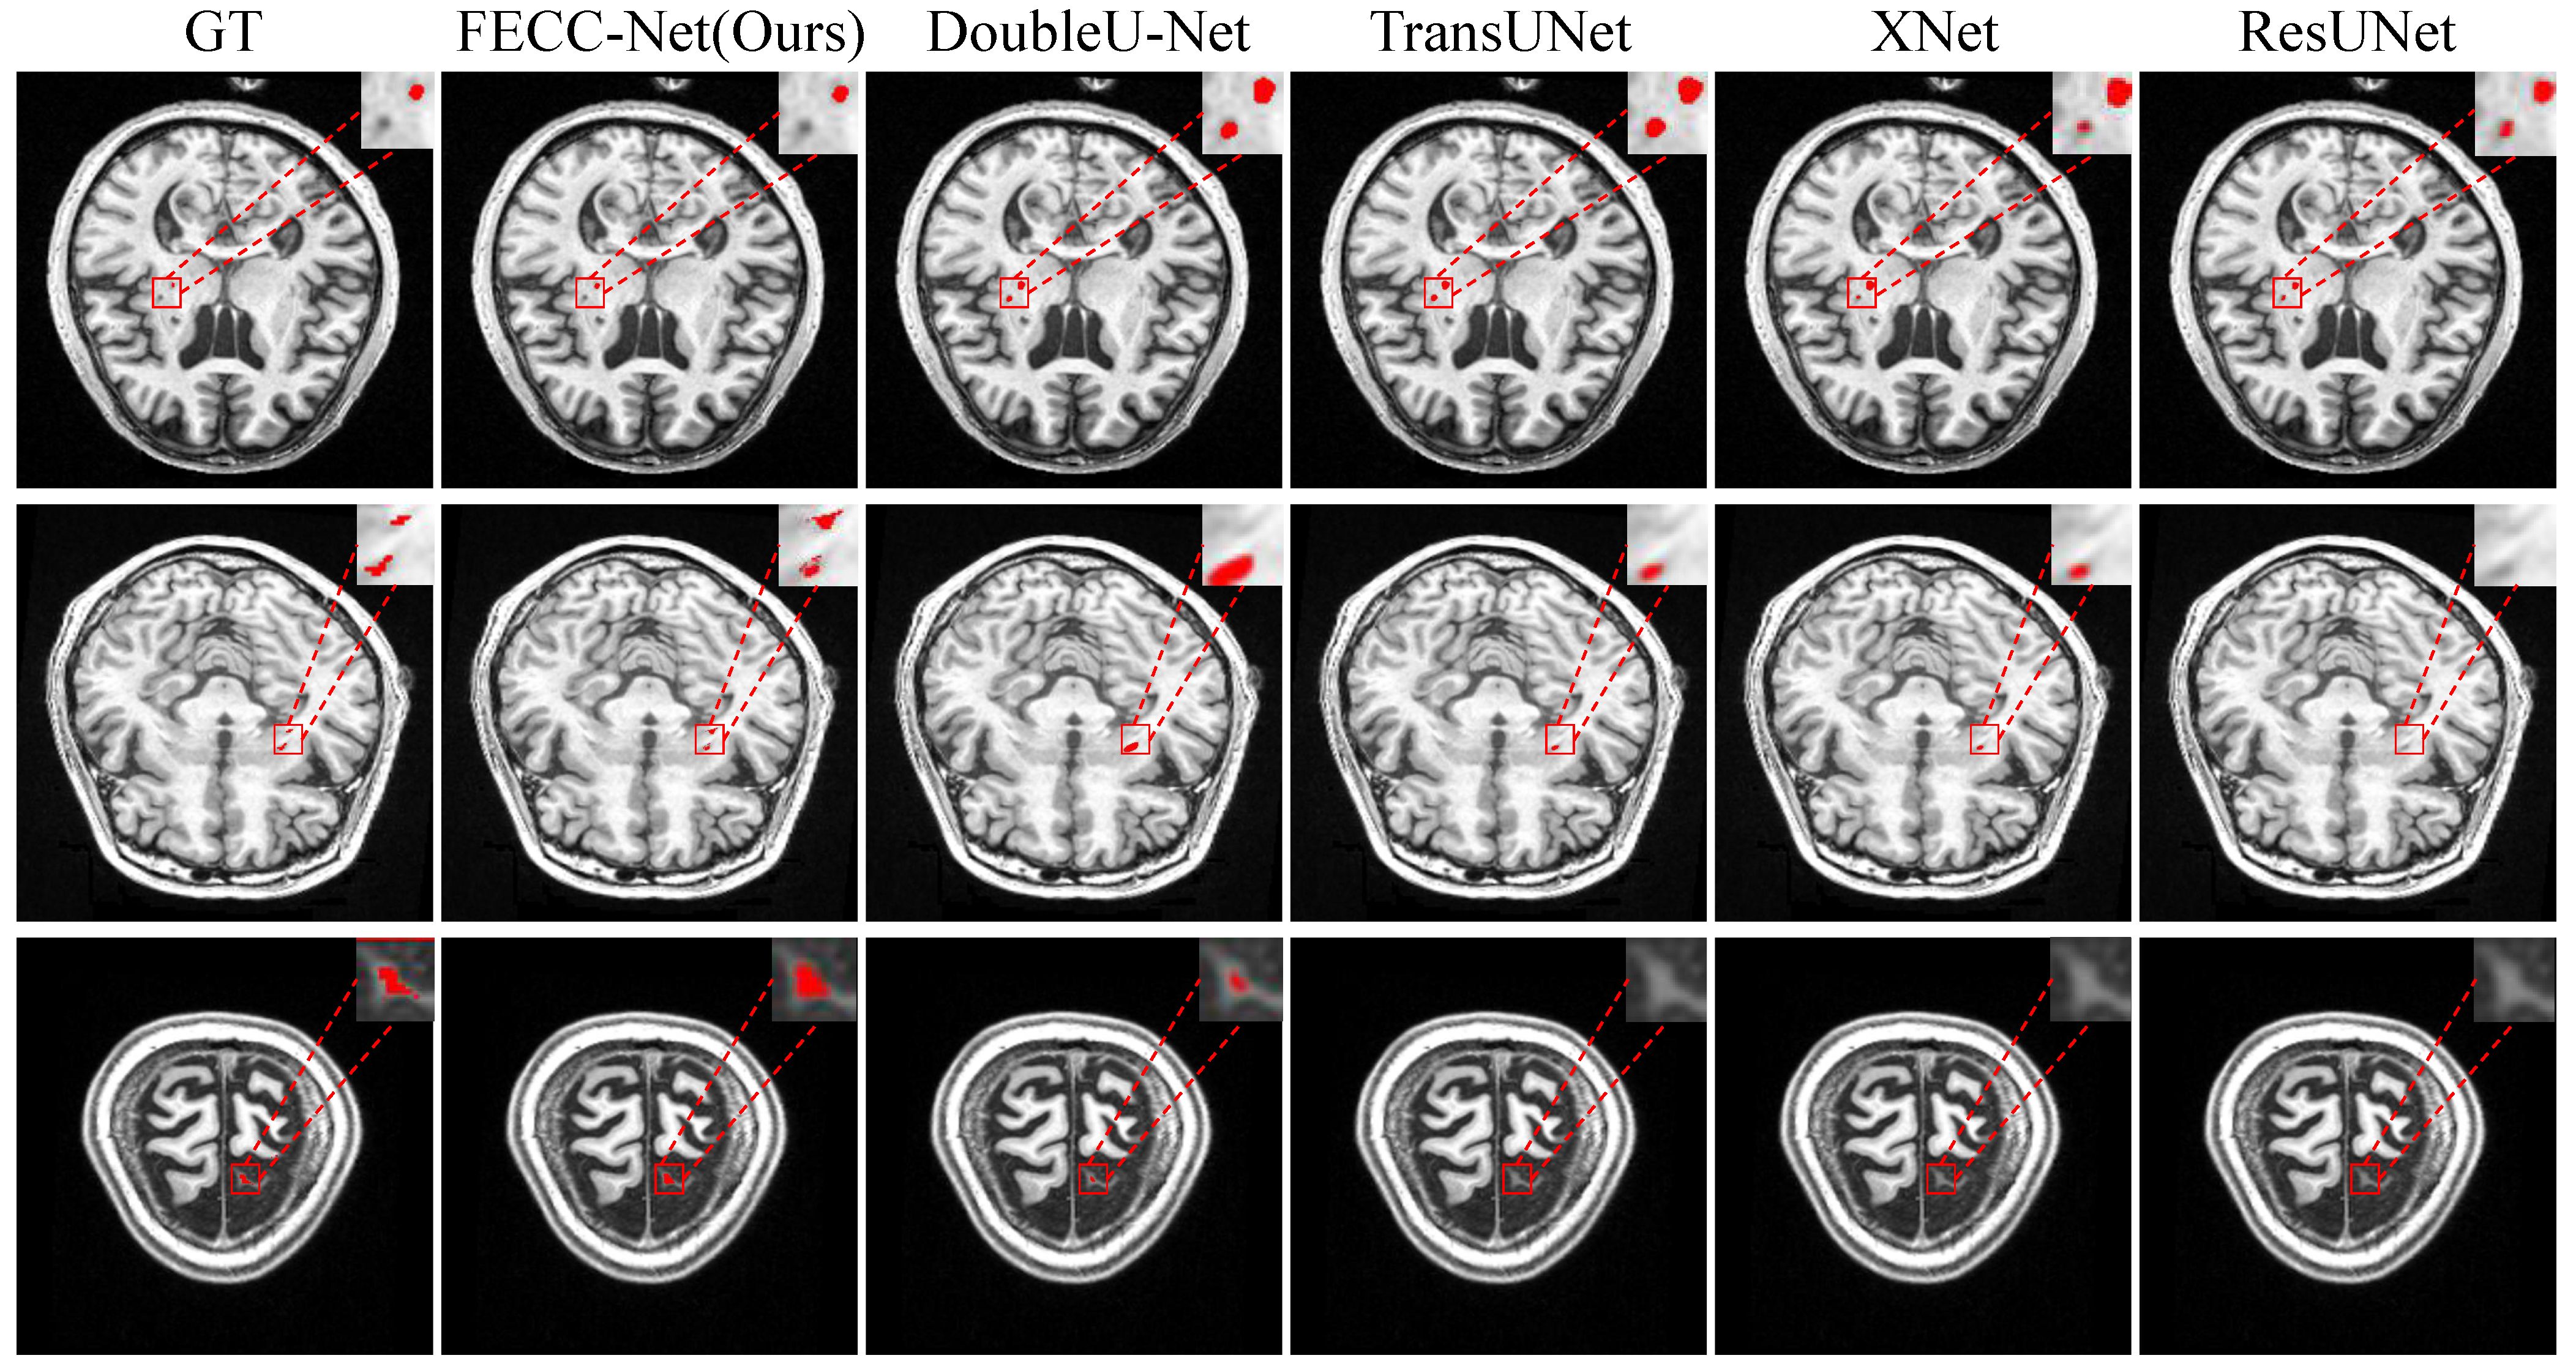

As shown in Figure 3, small target lesions in brain MRI images are difficult to distinguish with the naked eye and are mainly divided into two cases: missed detection and false detection. The first case in Figure 3 shows that other medical image segmentation models are prone to mislocalization when encountering dark pixels, and FECC-Net shows good performance. Hybrid loss plays an important role; it is effective. The training of the avoidance model tends to interfere with regions. The last two cases in Figure 3 mainly have the problem of missed detection. There are two reasons for such a problem: (1) insufficient extraction of deep features or (2) insufficient extraction of contextual information. FECC-Net does not experience loss of small target localization because the enhanced encoder ensures the depth of the network and its ASPP structure effectively capture contextual information through multi-scale fusion.

The second case was conducted on the medium target from ATLAS. From Table 3, we can see that FECC-Net outperforms TransUNet by 2.96% in DSC and 4.02% in mIoU on the medium target from ATLAS. As can be observed from Figure 4, the medium targets are mainly divided into two cases: the first case is the scattered lesions, and the second case is the slender lesions. In scattered lesions, the phenomenon of missed detection occurs easily when the dispersion distance is long, and it is easy to predict the scattered lesions as a connected overall lesion when the dispersion distance is short. In slender lesions, loss of lesion prediction is common. It turns out that both TransUNet and DoubleU-Net have the aforementioned series of problems. However, FECC-Net extracts context information while ensuring depth information, so it is more accurate for the localization of lesions.

The third experiment was conducted on the large target task. As indicated in Table 4, FECC-Net achieves a DSC of 0.9072 and mIoU of 0.8311, which are 1.85% and 1.39% higher than those of DoubleU-Net, respectively. The large object task is the most common case in life, which fully reflects the advantages of our proposed method. The three cases in Figure 5 show three challenges that are prone to large-objective tasks: (1) interference from redundant information, (2) loss of localization of discrete lesions, and (3) abnormal recovery of the edge of the lesion. The proposed algorithm solves the problem of low recall caused by redundant information through hybrid loss, solves the problem of discrete lesion localization via feature fusion of different scales through the ASPP structure, and solves the problem of abnormal boundary restoration through the enhanced encoder to enhance boundary features.

Figure 3. Qualitative result on small target from ATLAS. Typical small targets of stroke are difficult to find with the naked eye.

Figure 4. Qualitative result on medium target from ATLAS. Typical medium targets of stroke are often detected abnormally in discrete lesions and elongated lesions.

Figure 5. Qualitative result on large target from ATLAS. Typical large-target tasks in stroke are easily disturbed by shadowed areas, resulting in abnormal recovery at the edge of the lesion.